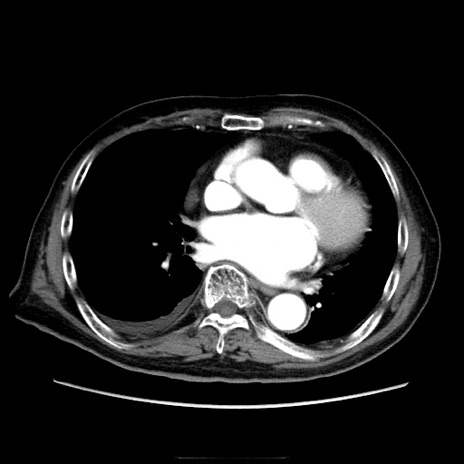

症例21(横断像)

【症例】70歳代男性

【主訴】腹痛

【現病歴】肝硬変・肝細胞癌にてかかりつけの方。約9時間前に食後より腹痛出現。症状が徐々に増悪し、嘔吐出現したため来院。

【既往歴】肝硬変、肝細胞癌(RFA、TACE後)

【身体所見】意識清明、表情苦悶様、BT 36℃、BP 129/78mmHg、P 88bpm、SpO2 97%(RA)、右上腹部から心窩部にかけて圧痛あり、反跳痛なし、筋性防御あり。

【データ】WBC 5800、CRP 0.16